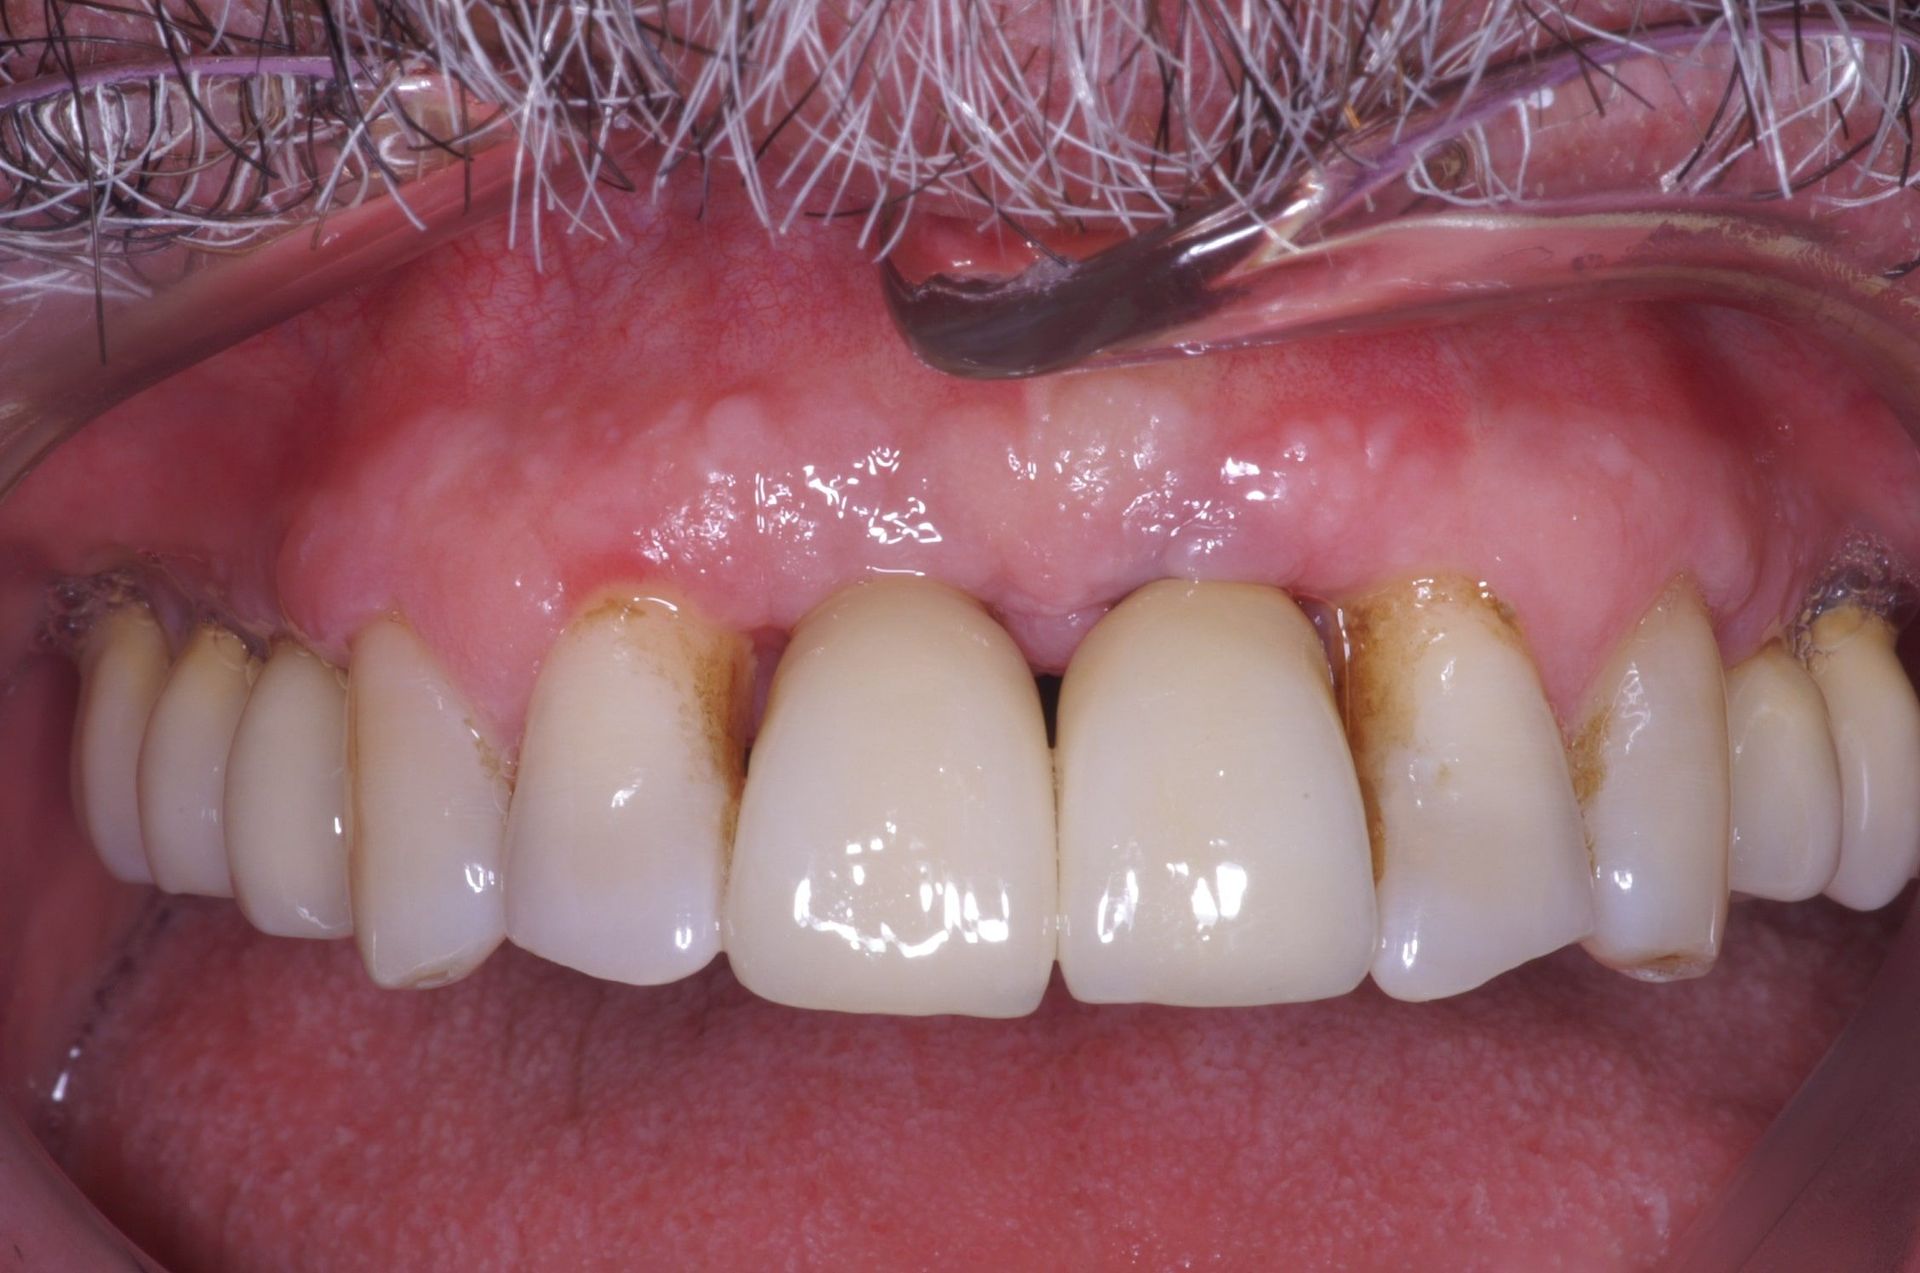

Avant et après greffe de gencive